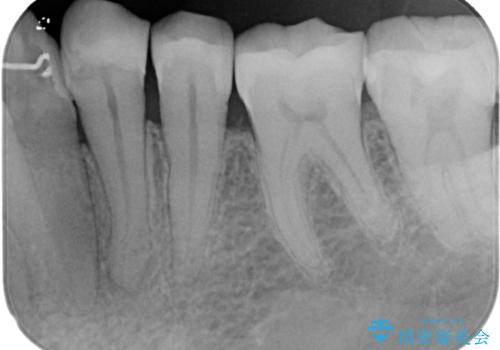

精査の結果、左下の第一小臼歯の虫歯が大きく進行していることが原因で痛みが出ていることがわかりました。

ラバーダム防湿を行ったうえで根管治療を行い、その後オールセラミッククラウンによる補綴治療を行っていくこととしました。

根管治療後すぐに痛みは消失しました。

根管治療後はクラウンによる補綴治療が必要です。